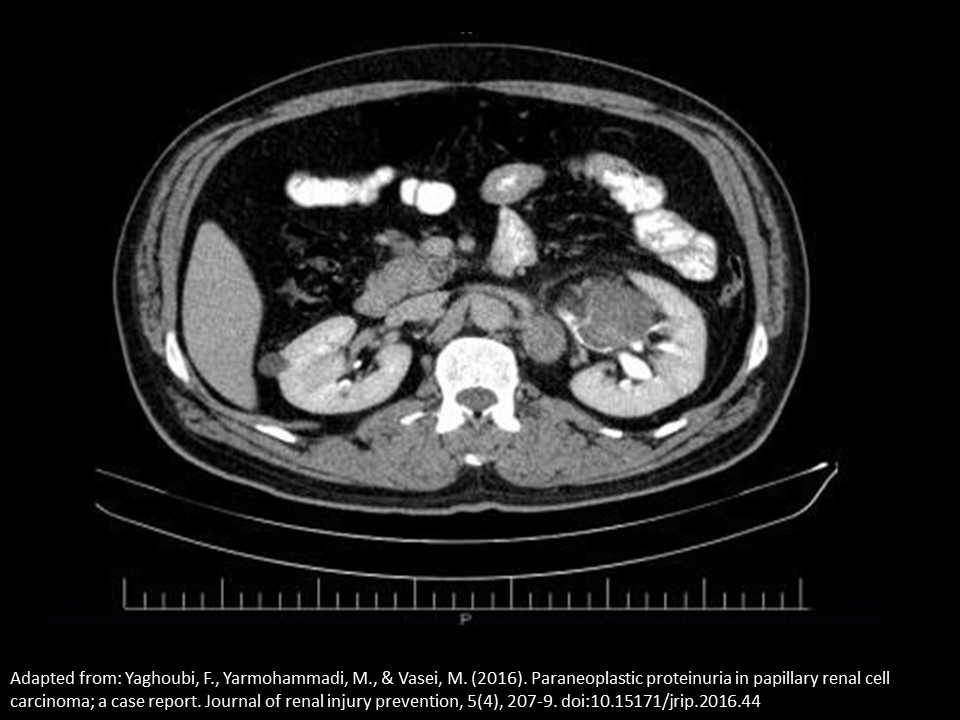

a patient is referred for an abdominal ultrasound due to an abnormal CT scan. The report is not available yet, but the study is in the PACS system. Based on this single CT image, where will you scan to evaluate an abnormality identified on the CT exam?

Anterolateral right kidney